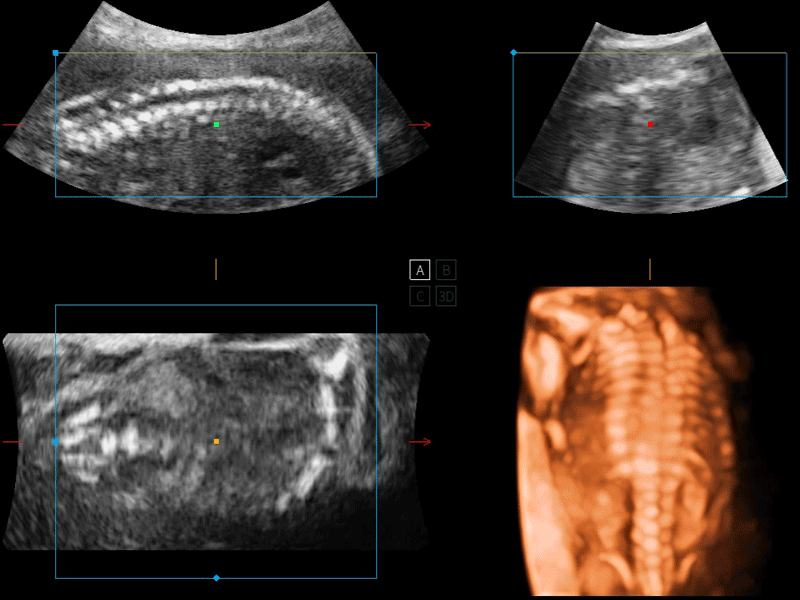

P12 Plus

彩色多普勒超聲診斷系統(tǒng)

開立醫(yī)療通過不斷的技術(shù)創(chuàng)新,為大眾的生命健康提供持續(xù)關(guān)愛。P12 Plus采用全新一代超聲成像平臺,新平臺旨在將真實(shí)還原組織解剖結(jié)構(gòu)作為首要目標(biāo)。平臺采用全新集成化硬件模塊,搭載新一代芯片,系統(tǒng)性能得到大幅提升,為您的診斷提供了豐富的臨床信息。優(yōu)異的圖像表現(xiàn),豐富的探頭配置,全面的應(yīng)用功能,為您日常診斷提供了可靠的助手。